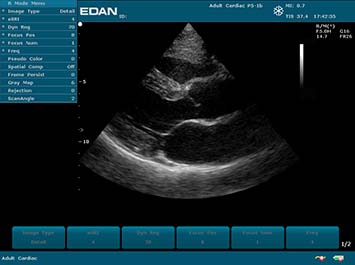

Клинические изображения